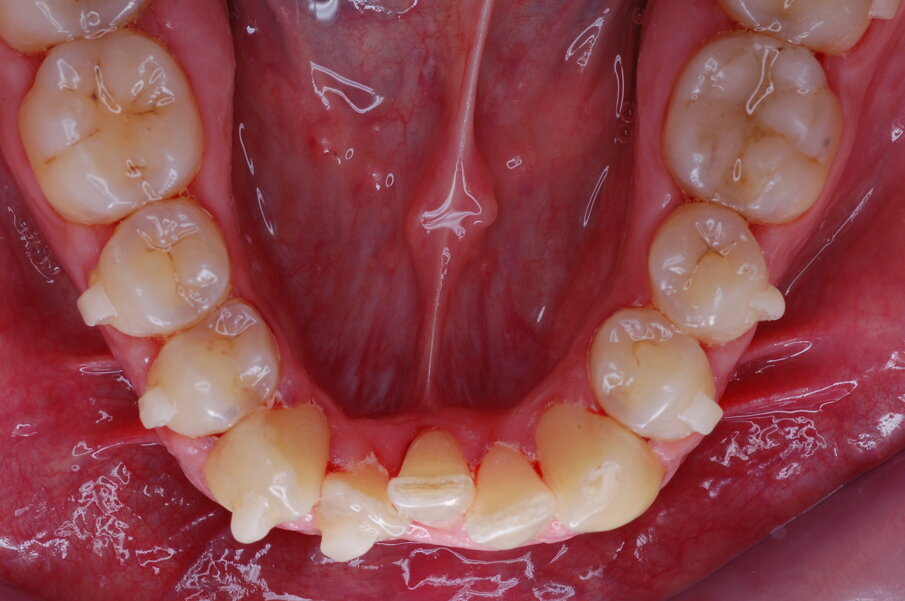

Diagnosi ed eziologia Un uomo sano di 39 anni si è presentato nel nostro studio ortodontico lamentando un aspetto dentale poco attraente e la paura della chirurgia ortognatica proposta da un altro ortodontista. Clinicamente, il profilo del paziente era rettilineo e la vista frontale non mostrava alcuna asimmetria facciale. L’esame funzionale non ha rivelato alcuna deviazione mandibolare o riduzione dei movimenti. Il paziente non aveva dolori articolari e non sono stati rilevati rumori articolari. Era presente una lieve occlusione molare bilaterale di Classe II, un morso aperto e un grave affollamento in entrambe le arcate. L’affollamento era particolarmente grave nell’arcata mandibolare, sebbene mancasse l’incisivo centrale mandibolare destro. Gli incisivi mascellari erano di piccole dimensioni, suggerendo una discrepanza dell’indice di Bolton se fossero stati presenti tutti e quattro gli incisivi mandibolari. Erano inoltre presenti un morso incrociato nella regione dell’incisivo laterale superiore sinistro e una grave rotazione distale del secondo premolare mandibolare sinistro (Figg. 1-8).

Figg. 1-8_Fotografie facciali e intraorali pre-trattamento.